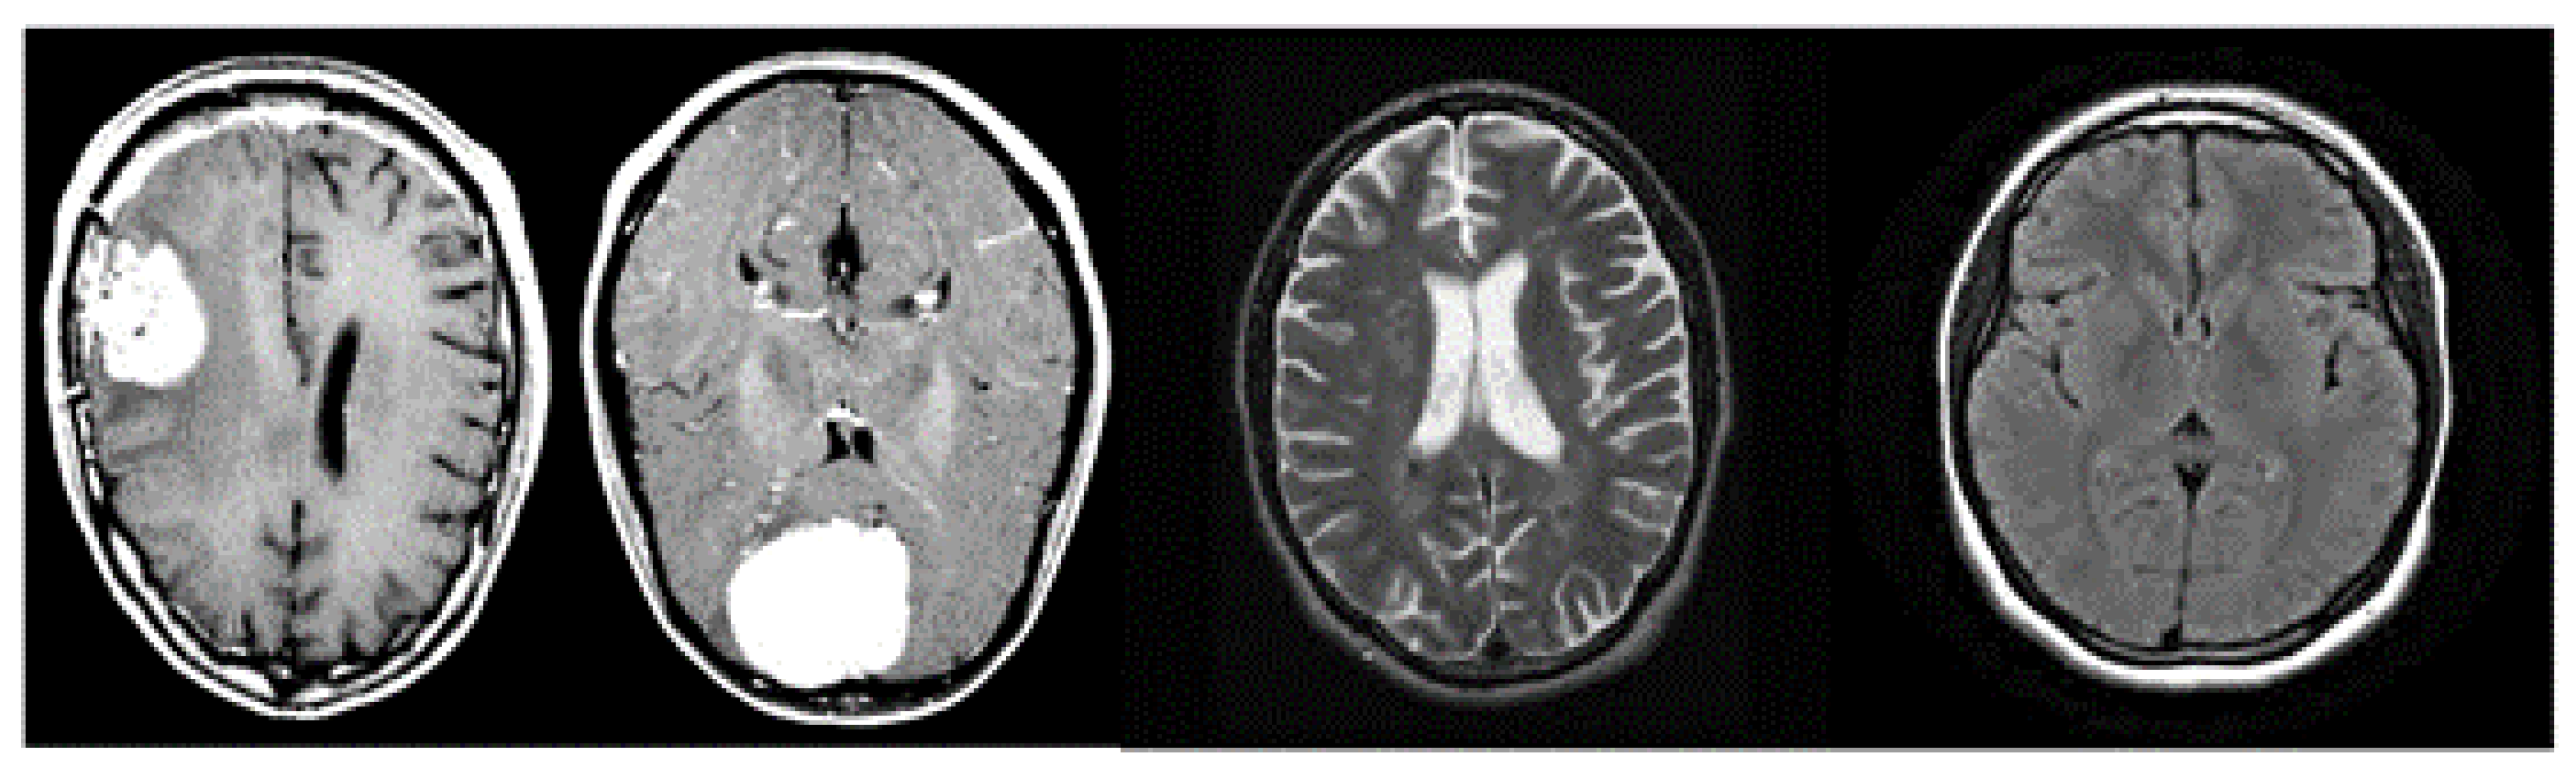

Figure 2 shows a set of images belonging to the analysed dataset; we can note that the images have a single angle (i.e., the one transversal to the height of the cortex).

Figure 2.

Examples of images belonging to the analysed dataset.